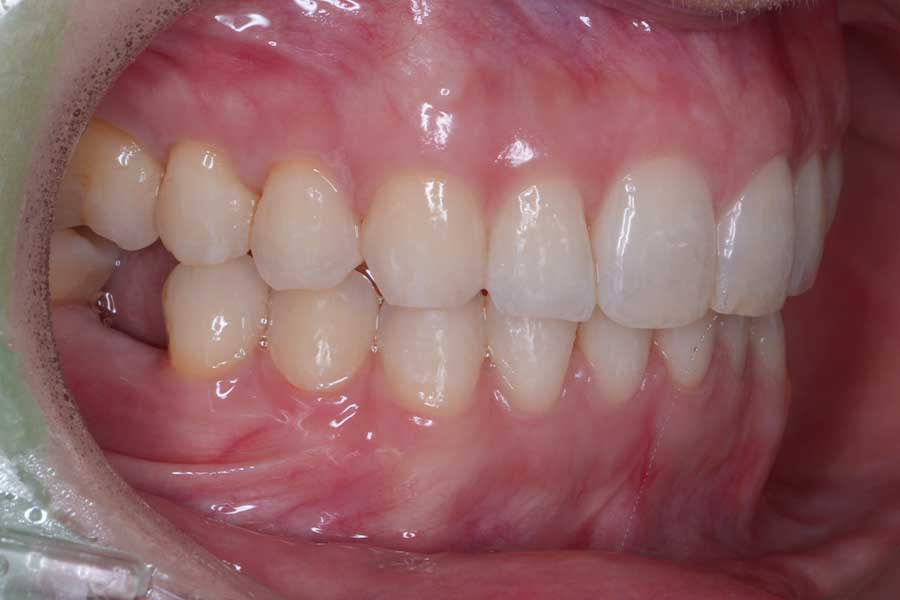

治療前

主訴 インプラント治療前にブラックトライアングルを消したい

治療内容 上下顎ラビアル矯正(表側矯正)